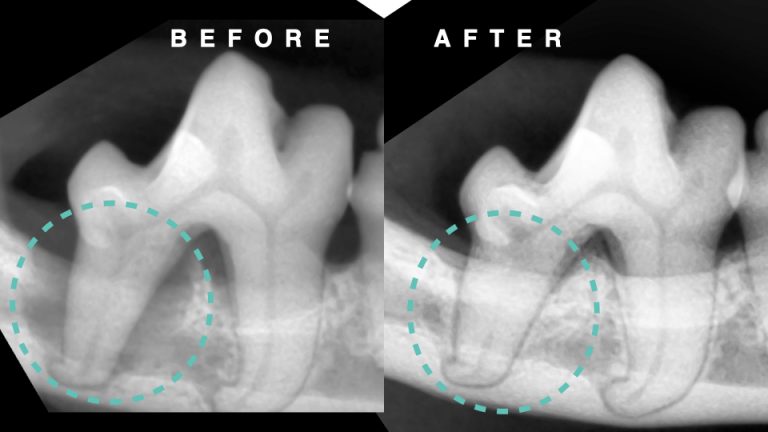

【歯科】猫の歯周病治療⑧

【歯科】歯石除去が早いほど良い理由⑥

【歯科】歯を温存するために歯周組織再生治療を行なった症例10

【歯科】歯を温存するために歯周組織再生治療を行なった症例⑨